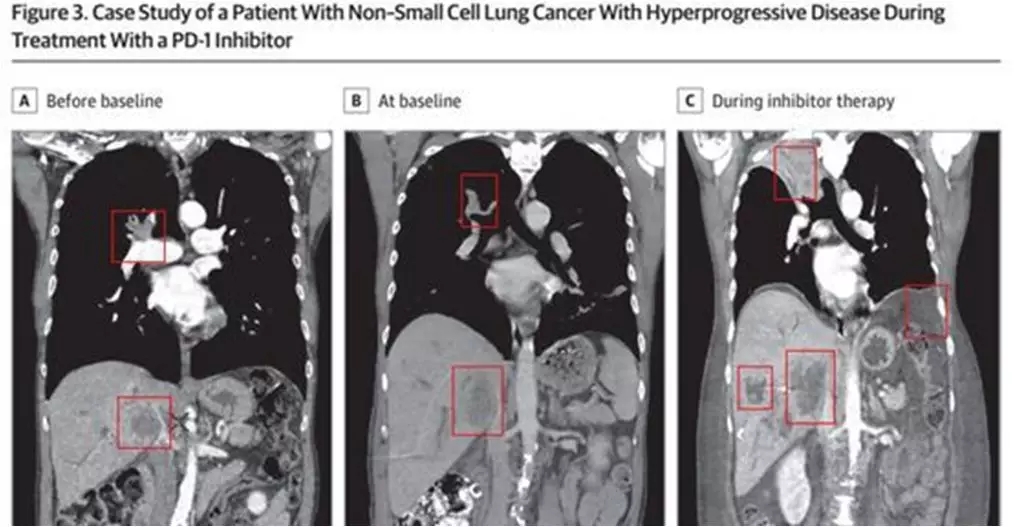

超进展(hyperprogression)是相对于“进展”而言,目前尚无标准的定义。综合目前的文献,超进展被定义为肿瘤反常的加速生长,包括:1.在免疫检查点抑制剂治疗后第一次评价时进展,或至治疗失败时间(TTF)﹤2月;2.肿瘤体积增加>50%;3.肿瘤增长速度(TGR)增加>2倍。

超进展引起轰动,2017年初发表在ClinCancer Res上的一篇文章指出,超进展在接受免疫检查点抑制剂治疗的患者中的发生率约为9%,而在老年患者(>65岁)中则为19%;免疫治疗导致的超进展与肿瘤负荷、肿瘤类型、治疗线数、PD-L1表达水平无相关性,和高龄(>65岁)、差OS相关;主要见于PD-1/PD-L1抑制剂,但PD-1抑制剂和PD-L1抑制剂在导致超进展发生方面也无明显差异。9%,这已经是个不低的数字了!19%,这已经是一个惊人的数字了!而且,此文报道的患者并不仅限于NSCLC,而是包含20个不同的瘤种。在文中,作者还专门写道:另有18名患者因为在第一次评价疗效之前就出现了明显的临床进展,所以并未纳入统计,因此实际上发生超进展的频率可能远比9%要高。果然,随后的Lancet杂志就发表评述文章,把超进展比作了“可怜的阿喀琉斯”,脚踝又一次被无辜射中了。

一项多中心队列研究,在2017年ESMO年会上,法国学者Singavi回顾性收集了5个研究中心从2012年11月至2017年3月期间242例接受免疫治疗的晚期NSCLC患者的临床和影像学数据,进而评估超进展的发生率,并指出超进展为患者的预后不良因素,超进展患者的中位OS仅为 3.5个月。

紧随其后,在2017年第18届WCLC上也发表了关于超进展的报道。法国学者Ferrara等对接受晚期NSCLC治疗的患者进行了回顾性分析。研究人员回顾性收集了5年(2012年至2017年)8个不同机构接受过免疫治疗的333例晚期NSCLC患者的数据,中位随访期为12个月;在这些患者中,14%患者发生了超进展,OS仅为3.4个月。